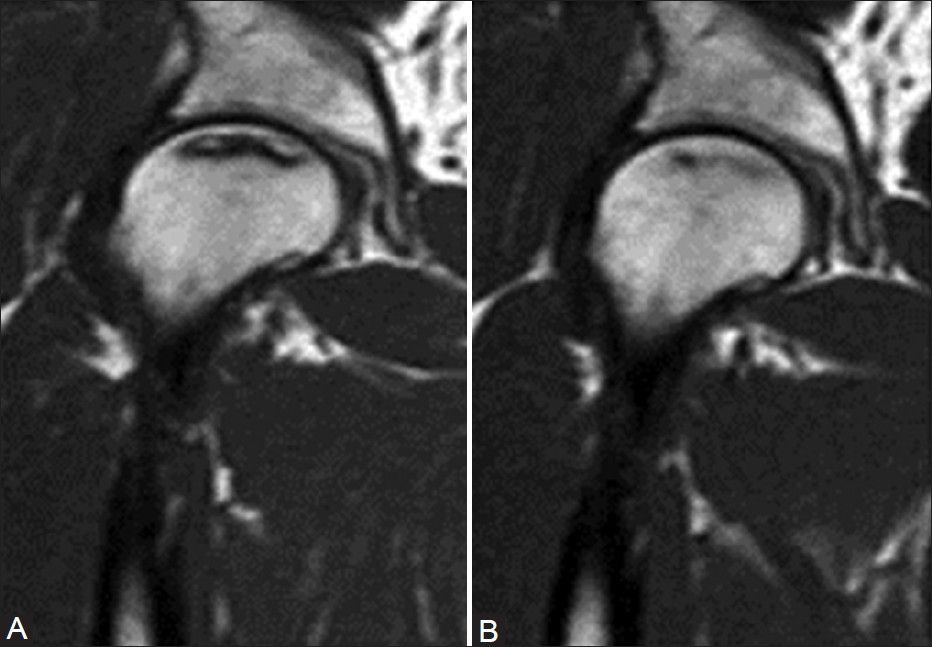

Background: This study analyzed the long-term outcomes of extracorporeal shockwave therapy (ESWT) and core decompression for early osteonecrosis of the femoral head (ONFH) with 8- to 9-year follow-up.

Methods: The study cohort consisted of 48 patients with 57 hips including 23 patients with 29 hips in the ESWT group and 25 patients with 28 hips in the surgical group. Patients in ESWT group received shockwave therapy to the affected hip. Patients in surgical group underwent core decompression and autogenous cancellous bone and allogenous fibular graft. The average length of follow-up was 103.5 3.4 (ranged 93-106) months and 104.54.3 (ranged 95-108) months for the ESWT and the surgical group, respectively. The evaluations included clinical assessment for pain and function, X-ray and MRI of the affected hips.

Results: The overall clinical results were 76% good or fair and 24% poor for the ESWT group; and 21% good or fair and 79% poor for the surgical group. THA was performed in 3% and 21% at one year, 10% and 32% at 2 years and 24% and 64% at 8-9 years for ESWT and the surgical group respectively. Significant differences in pain and Harris hip scores were observed at different time intervals favoring the ESWT group. There was a trend of decrease in the size of the lesion in the ESWT group when compared with the surgical group.

Conclusion: ESWT appears to be more effective than core decompression and bone grafting for early ONFH with 8- to 9-year long-term follow-up.